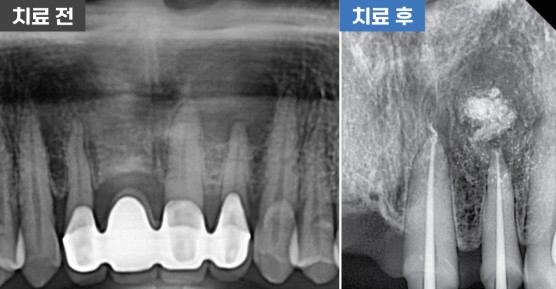

신경치료 및 치근단절제술

치료 기간 2021. 10. 15 ~2022. 02. 11

진단명 : 치근단낭

치료명 : 신경치료 및 치근단절제술

#12.X.21.22 cr 상태 #21.22 뿌리밑 염증, Fistula 있음